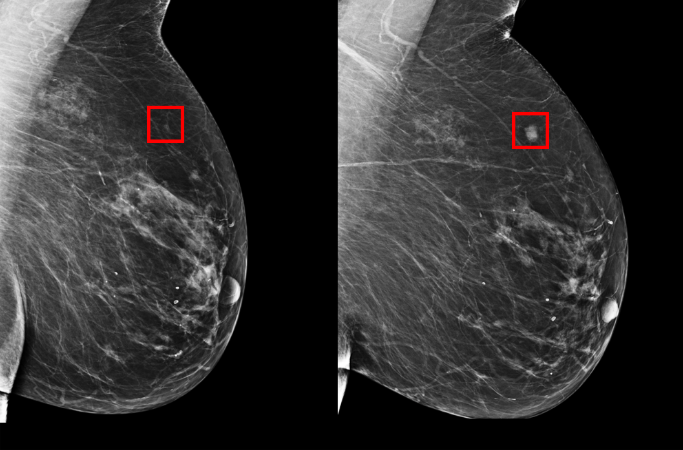

MIT 컴퓨터과학·인공지능연구소 CSAIL이 매사추세츠종합병원 연구팀과 AI를 이용한 새로운 유방암 엑스선 검사 방법을 개발했다. 심층 학습 모델로 학습한 AI는 5년 안에 ...